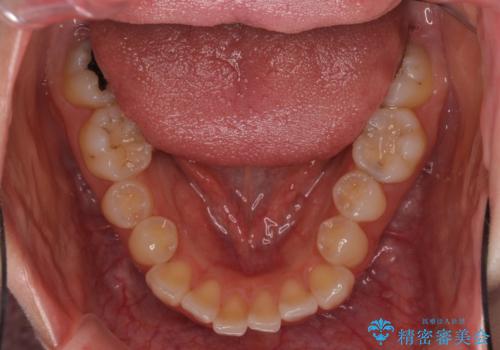

- 前歯のクロスバイトや残存している乳歯を気にして来院された患者様です。

上顎骨の幅が下顎骨よりも小さいので、拡大装置により骨幅を広げて上下関係を改善し、その後インビザラインにて歯並びを整えることとしました。

上下の骨幅を改善したことで、スムーズに歯列矯正を行うことができました。